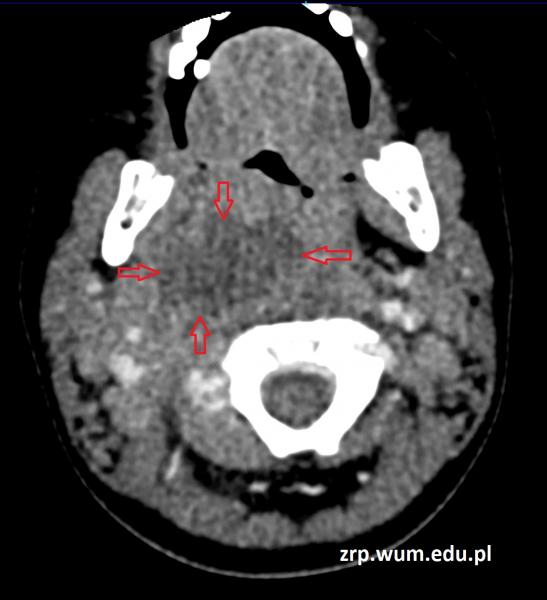

Przypadek 45: 2-letni chłopiec zgłosił się do IP z gorączką i apatią od 5 dni oraz zapaleniem węzłów chłonnych szyi. W badaniu przedmiotowym stwierdzono przesunięcie bocznej ściany gardła po stronie prawej, szczękościsk, przymusowe ustawienie głowy. Wysunięto podejrzenie nacieku zapalnego przestrzeni przygardłowej po stronie prawej. Wykonano TK szyi w celu wykluczenia ropnia pozagardłowego.

Rozpoznanie: W badaniu tomografii komputerowej w przestrzeni za- i przygardłowej po stronie prawej widoczny jest neregularny obszar płynowy - ropień (strzałki) - zmiana przemieszcza i modeluje naczynia szyjne, gardło dolne, krtań i przełyk.